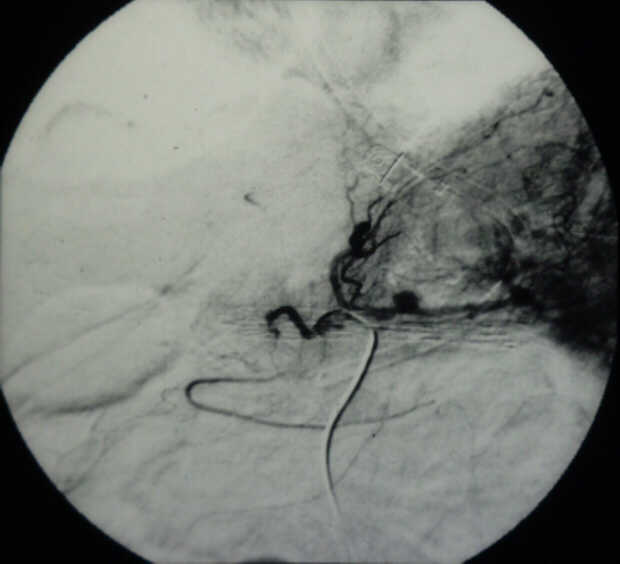

Diagnosis: Angiography

Giuseppe Morelli Coppola, Raffaella Niola, Franco Maglione

Unità Operativa di Radiologia Vascolare ed Interventistica, Azienda Ospedaliera "A. Cardarelli". Napoli, Italy